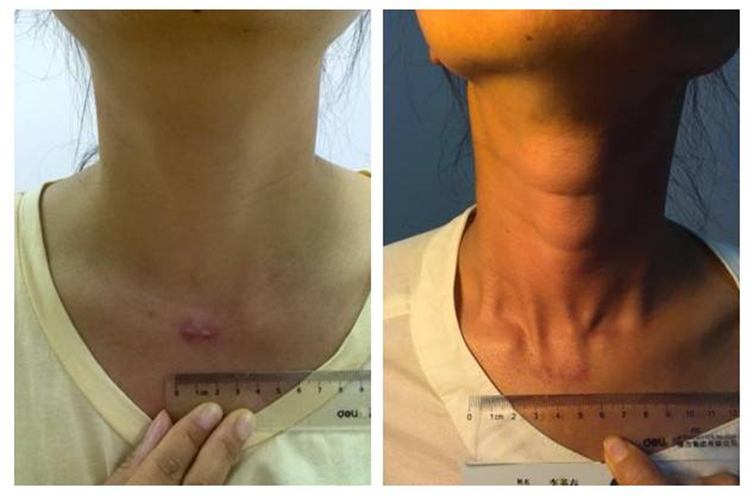

微創治療甲狀腺癌效果

女性甲狀腺癌